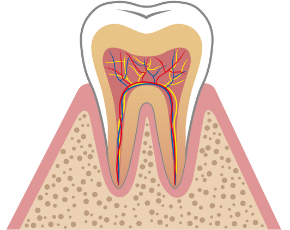

むし歯とは、お口の中のむし歯の原因菌が糖分を分解してネバネバになり、歯に付着してから、そこで「酸」を出し、その「酸」が歯の成分を溶かしていく病気です。ごく初期の段階を「脱灰(だっかい)」といいます。それは歯の表面のエナメル質の成分が溶け出す状態ですが、この場合は、「再石灰化(さいせっかいか)」で元に戻ります。しかし、その段階を過ぎると、むし歯はどんどん進行し自然には治りません。放っておくと歯の中の神経にまで汚染がおよび、やがては歯を失うことにもつながるのです。